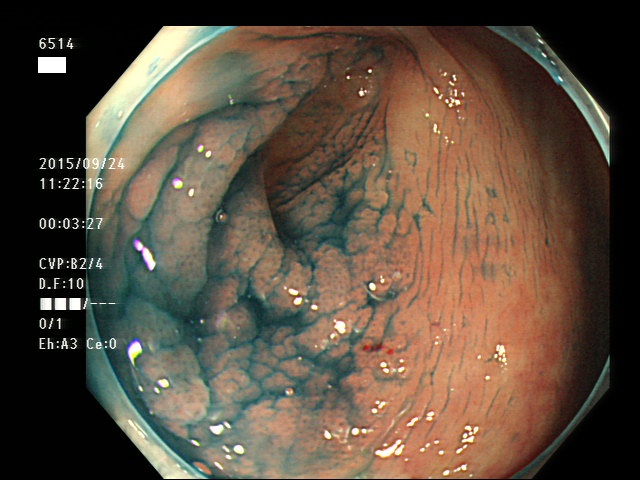

虫垂開口部の過形成ポリープ(SSAP)の例

虫垂にはSSAP(過形成ポリープ)ができ易い?

医師が熱心に探すようになったとは言え、それにしても虫垂SSAPは、よく見つかります。2016年の文献でSPS症候群の実に70%近くに虫垂のSSAPが合併すると報告されました。SPS症候群では大腸全体に 過形成ポリープが多発します。しかし、面積で大腸の極一部しか占めない虫垂に70%の確率でSSAPが合併するのは明らかに「多すぎ」です。虫垂は、大腸の他の部位よりもSSAPが出来易いと言えます。SSAPの発生に長期の炎症が関与しているという報告があります。虫垂は慢性的な炎症を起こすことが多いためにSSAPが出来易いのかもしれません。